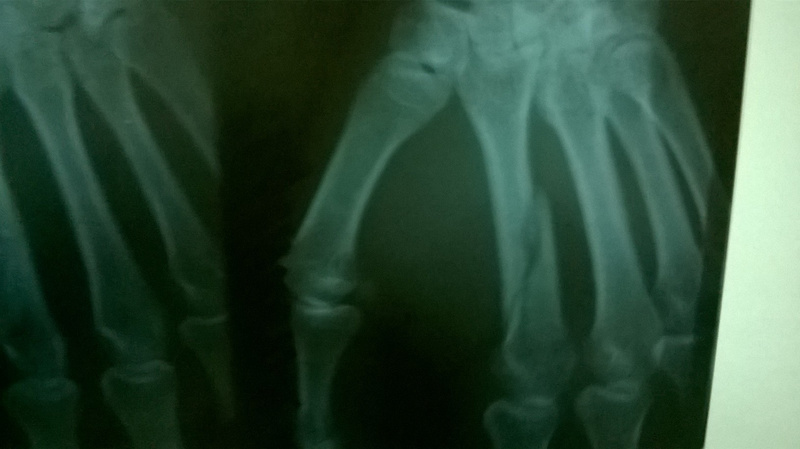

Все равно пошел в травму (травмпункт дзержинского района в ГКБ №2), на снимке - косой перелом второй пястной кости. Мне показалось, что со смещением, врач сказал: нормально, остность сохранена, все зарастет. Привязывают лангету, отпускают.

И вот я иду на очередной плановый рентген (рентгенкабинет на пр. Дзержинского, 15), мне выдают снимок с описанием, в описании сказано: "Слабо консолидированный косой перелом 2 пястной кости со смещением на ширину кортикального слоя". Иду к врачу Круппа в ГКБ№2, он опять мне говорит, что все нормально, мол на шишку в кисти не обращай внимания, все заживет. На вопрос: "почему за месяц не зажило" (перелом слабо сросшийся) говорит: еще две недели походи в гипсе, и все будет нормально, ну, шишка у тебя останется.

Конкретно тот, который я выложил, сделан через 27 дней после травмы. Есть еще два, самый первый через 7 дней после травмы, и последний через 35 дней после травмы.

Перелом срастется в том же положении, что и на рентгене, т.е в смещенном. Шишка на руке останется. Первое время после снятия лонгеты может быть снижение силы в руке, но если заниматься (эспандер жать к примеру) быстро восстановится. В конечно счете будет только косметический дефект, так что вам решать ,ходить так или оперировать и ставить кость на место.